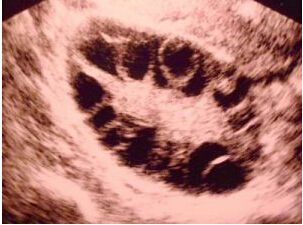

多囊卵巢综合征形成的原因具体有哪些呢?多囊患者在备孕这条道路上真的是有苦难言,很多患者往往由于排卵障碍导致生育困难。

多囊卵巢总体来讲是由复杂的内分泌失调以及新陈代谢异常导致的疾病。多囊卵巢早期的时候会出现闭经的现象,严重的还会出现不孕不育的症状,所以一定要及时就医,特别是年轻的女性,想要怀孕的情况下,需要先面诊专业的医生之后才能做备孕哦。多囊患者在治疗之后备孕无果选择试管,积极听取生殖医生的建议也是可以成功做试管婴儿的。